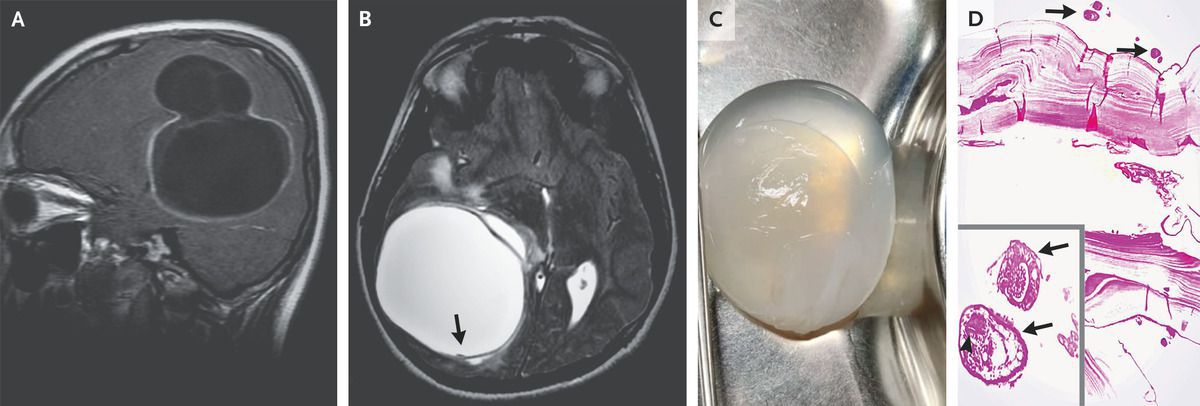

A previously healthy 14-year-old boy who lived on a farm presented with a 1-month history of episodic headaches associated with vomiting. Physical examination was notable for papilledema. Magnetic resonance imaging of the head showed a multiloculated cyst measuring 6.0 cm by 6.2 cm by 5.8 cm in the right temporoparietal region of the brain (Panel A, sagittal view, T1-weighted) with a hypointense rim and small projections in T2 phase (Panel B, axial view, arrow), findings suggestive of cystic echinococcosis. Computed tomography of the body showed no other sites of disease. A craniotomy was performed to excise the cyst. Saline irrigation was used to separate the cyst wall from the brain to avoid rupture (Panel C and video). Histopathological examination revealed an echinococcal laminated membrane lined by a germinal layer with daughter cysts (Panel D, arrows) and protoscolices (inset, arrows) with hooklets (arrowhead). A diagnosis of primary cerebral cystic echinococcosis from Echinococcus granulosus was made. Echinococcal cysts — also called hydatid cysts — most commonly form in the liver. The infection is transmitted to humans through contact with infected livestock or canine feces, as was likely to have happened in this case. Symptoms evolve if the cysts exert a mass effect. A 3-month course of albendazole was prescribed at discharge. At the 2-week follow-up, the patient’s symptoms had resolved. Sumit Thakar, M.B., B.S., M.Ch. Akhil Sunil, M.B., B.S., D.N.B. Sri Sathya Sai Institute of Higher Medical Sciences, Bangalore, India source: nejm.org